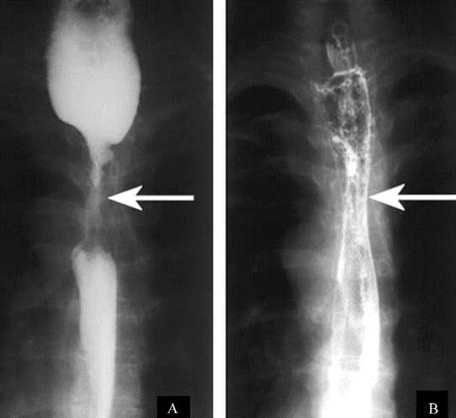

1.7.20.1.5(五)内镜下消化道狭窄的治疗